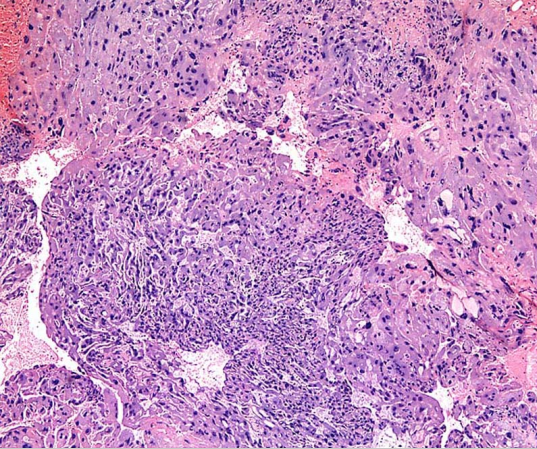

绒癌的大体观见肿瘤位于子宫肌层内,可突向宫腔或穿破浆膜,单个或多个,大小不等,无固定形态,与周围组织分界清,质地软而腌,海编样,暗红色,伴明显出血坏死。镜下见肿瘤细胞由细胞滋养细胞、合体滋养细胞及中间型滋养细胞组成,成片状高度增生,明显异型,不形成绒毛或水泡状结构,并广泛侵入子宫肌层造成出血坏死。肿瘤不含间质和自身血管,瘤细胞靠侵蚀母体血管而获取营养。

绒癌大体观 绒癌镜下观(200×)

肿瘤由细胞滋养细胞及合体滋养细胞组成, 看不到绒毛,伴出血坏死